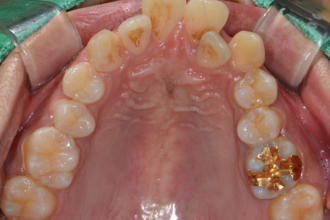

치아교정

굿프렌즈 치과 임상 케이스

직접 확인해보세요!